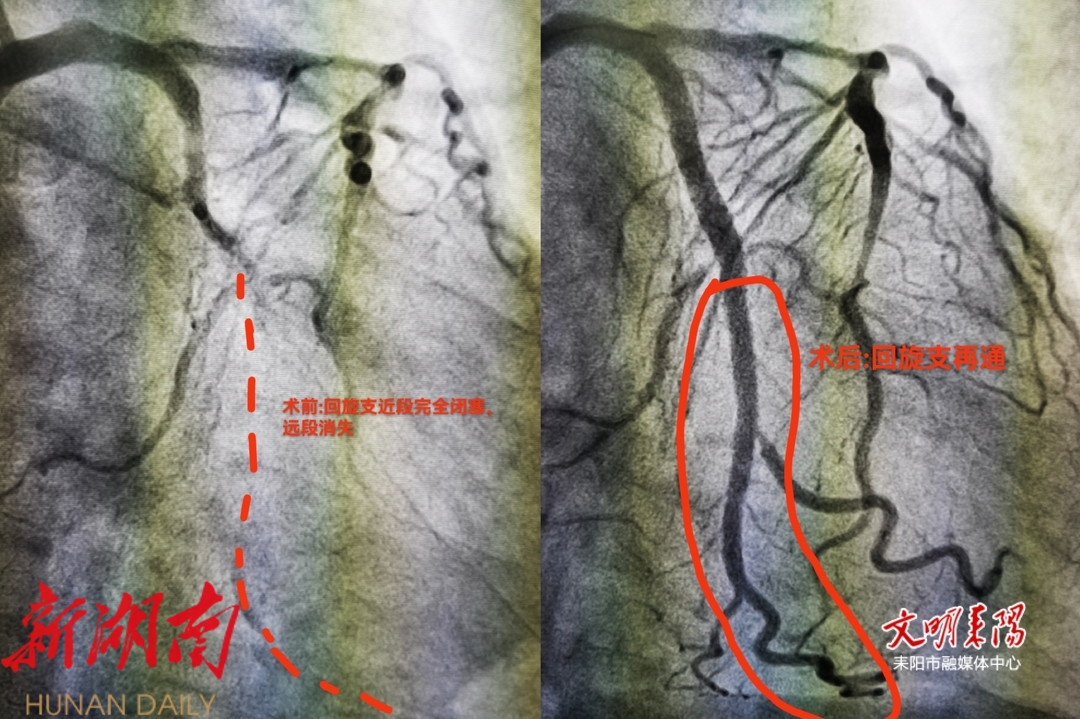

在呼吸机的支持下,患者被紧急转运至导管室,冠脉造影显示患者右冠中段慢性完全闭塞,前降支近段重度狭窄,而回旋支近段急性完全闭塞——正是这处血管急性闭塞引发了心脏骤停。心内二区副主任医师谢求德主刀、副主任医师杨忠协助,团队同步调取影像数据精准研判,麻醉科精准调控生命体征,迅速在回旋支植入两枚支架,仅用40分钟便成功开通血管。术后MDT团队无缝衔接,心内二区与ICU就抗凝方案、循环支持等关键环节反复推敲,全程护送患者至重症监护室。目前,患者已康复出院。